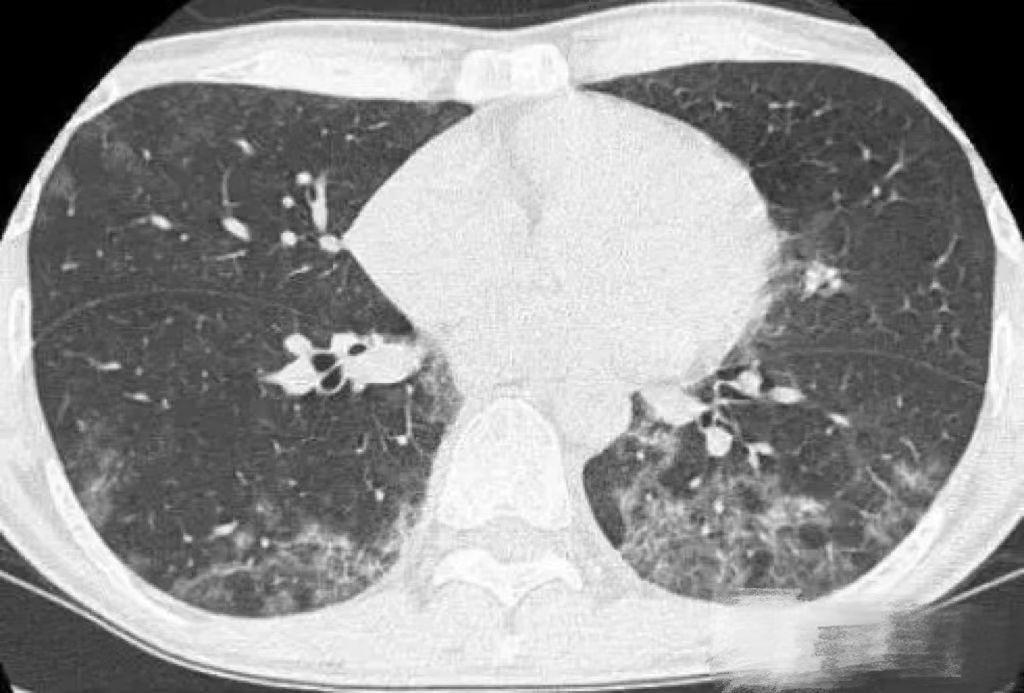

常见的临床表现为干咳、发热、气促、发绀、呼吸困难,若并发AIDS,患者多为亚急性起病,呼吸困难逐渐加重,严重者会发生呼吸窘迫。本病症状严重,但肺部体征少,多数患者肺部听诊无异常,部分患者可闻及散在湿啰音。患者的CT检查可显示双肺毛玻璃样改变,血气分析示低氧血症,严重者动脉血氧分压明显降低,常在60mmHg以下。患者一旦出现上述症状,应立即到医院就诊。目前病原学检测是PCP诊断的最准确标准。而通过对痰液、支气管肺泡灌洗液的染色镜检和PCR检测则是诊断PCP的主要方法。近年来,宏基因组二代测序技术(metagenomic next-generation sequencing,mNGS)在PCP的诊断中显示出了快速、准确的特点,也可作为诊断方法之一。此外,血清1, 3-β-D-葡聚糖、乳酸脱氢酶检测等也可作为PCP诊断的辅助指标。而高分辨胸部CT则是PCP影像学诊断方法。肺炎早期、进展期及转归期的CT表现不同,最后可发展为弥漫性间质性肺病。